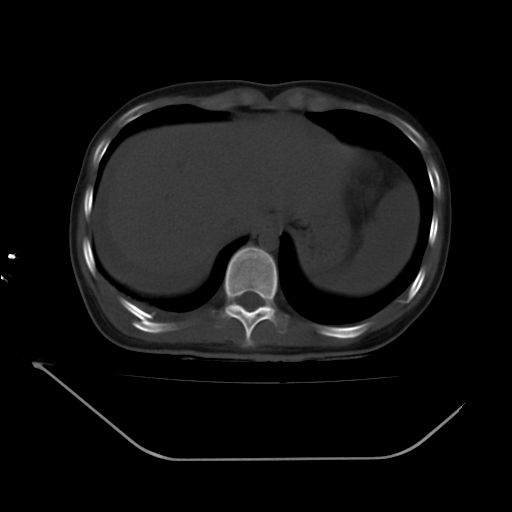

以下是引用liuyue在2008-7-19 13:02:00的发言:[br]1.肝右叶后下段及右肾挫裂伤伴腹腔积血。[br]2.右侧多发性肋骨骨折、横突骨折、右髂骨骨折伴周围软组织挫伤。[br]3.右侧腰大肌肿胀,并可见低密度影,如为气体,则肠道挫裂伤待除外。

以下是引用zhengfaming在2008-7-19 14:42:00的发言:[br]1.肝右叶后下段及右肾挫裂伤伴腹腔积血。脾脏挫裂伤待排[br]2.右侧多发性肋骨骨折、横突骨折、右髂骨骨折伴周围软组织挫伤。[br]3.右侧腰大肌肿胀,并可见低密度影,如为气体,则肠道挫裂伤待除外

以下是引用道哥在2008-7-19 16:52:00的发言:[br]肝右叶后下段及右肾挫裂伤、脾破裂伴腹腔积血。[br]2.双侧多发性肋骨骨折、横突骨折、右髂骨骨折伴周围软组织挫伤。[br]3.右侧腰大肌肿胀,并可见低密度影,如为气体,则肠道挫裂伤待除外。